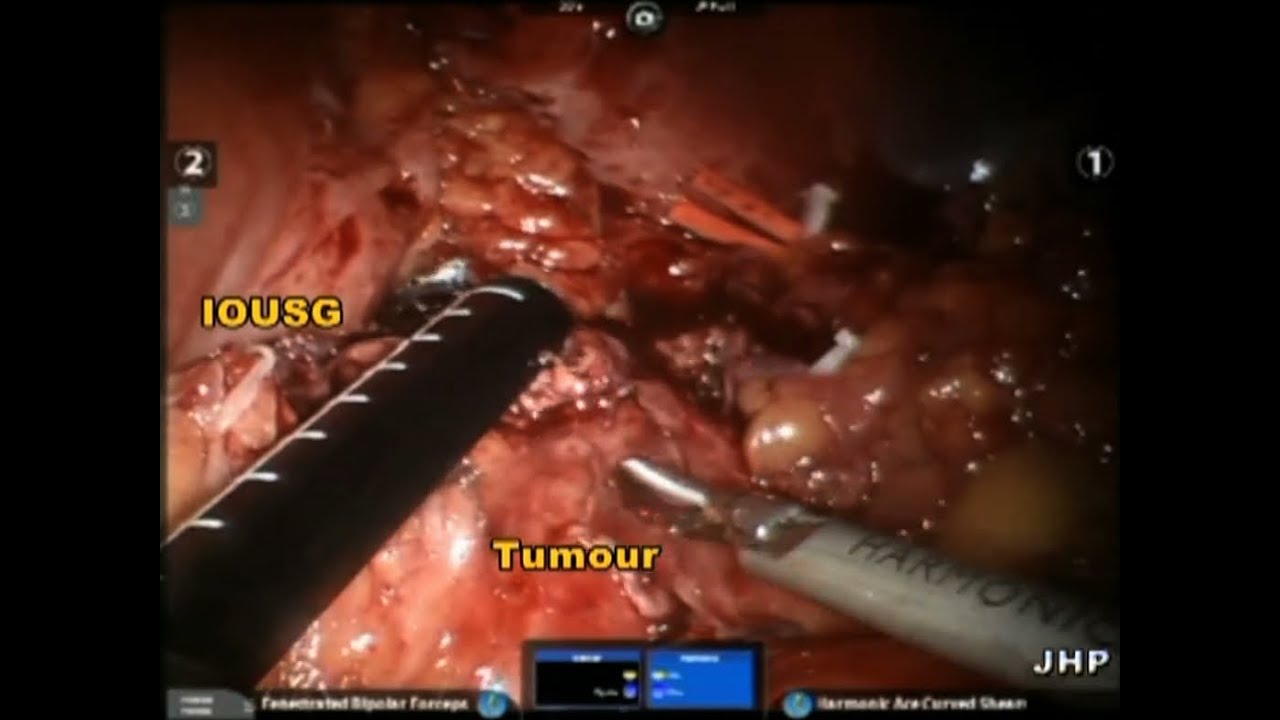

Robotic Enucleation of Renal Hilar Tumour

Robotic Enucleation of Renal Hilar Tumour